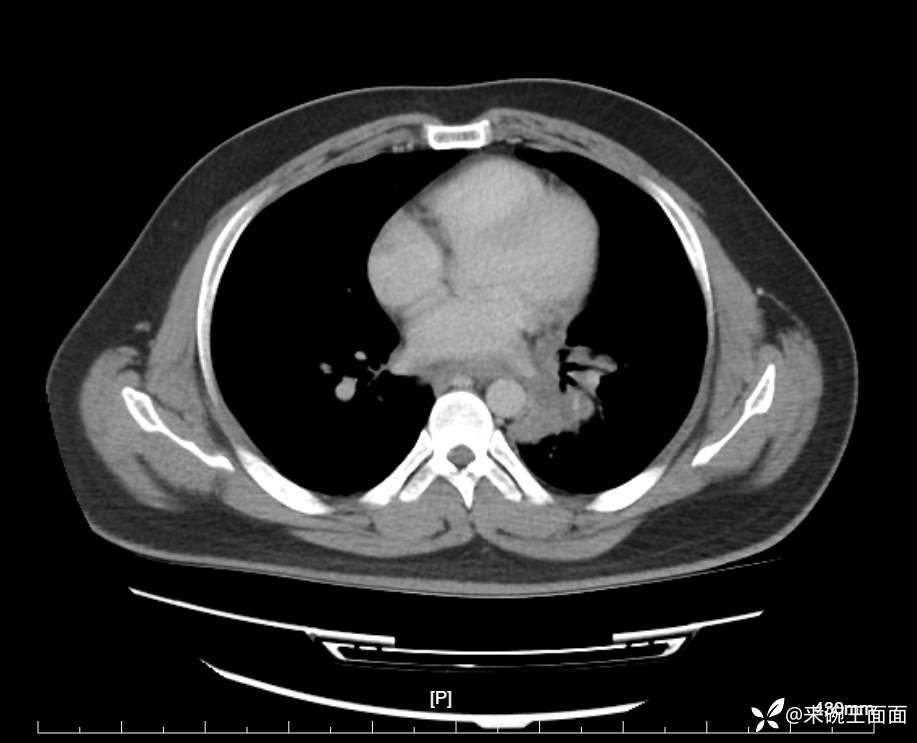

性别:男

年龄:27岁

主诉:胸闷胸痛数月余,休息后可自行缓解,无咯血症状。

个人史:数年吸烟史,具体不详。